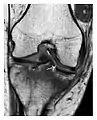

The greater tuberosity of the humerus is also an illustrative location of occult fractures. The osseous injury may follow seizures, glenohumeral dislocation, forced abduction, or direct impaction. They are commonly discovered on MRI in symptomatic patients with suspicion of rotator cuff tear. Coronal images are best suited for detection. They appear as crescentic oblique lines surrounded by a bone marrow edema pattern (Figure 5). The rotator cuff must be inspected since associated ligamentous lesions are common. In the ankle, malleoli and tarsal bones should be checked carefully for any cortical disruptions and radiolucent lines that may reveal a fracture. Awareness of the exact location of the pain will help direct the attention of the interpreter when searching for very subtle signs of fracture (Figure 6).[1]

a

b

Figure 7: Fatigue fracture of the talus in a 25-year-old male basketball player with right hind foot and ankle pain, without history of trauma, and a normal initial radiograph (not shown). (a) One-month followup lateral radiograph shows normal appearance. (b) Sagittal T1-weighted MRI shows an irregular fracture line (arrow) within an ill-defined area of hypointensity corresponding to bone marrow edema.[1]